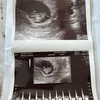

Kabar bahagia! Jessica Iskandar diketahui tengah hamil anak ketiga. Bedanya kehamilan wanita yang akrab disapa Jedar ini melalui program bayi tabung di salah satu rumah sakit di Surabaya, Jawa Timur.

Benny pun memastikan bahwa langkah Jessica dan Vincent melakukan program bayi tabung, bukan karena susah mendapatkan keturunan setelah melakukan program hamil secara alami. Tapi Jessica dan Vincent ingin bisa sesegera mungkin memiliki keturunan di tahun atau shio naga.